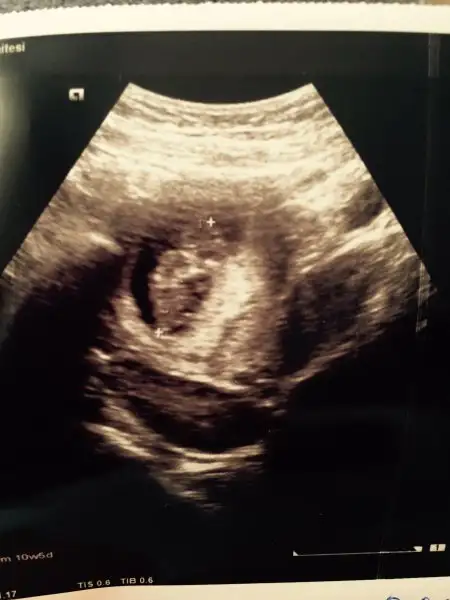

Hamdolsun iyi bebişim. 11+2 bugün normalde ama 11+5 çıktı ultrasonda.Ense kalınlığıda normal sınırda şükür. İkili test için 75 tl verdim özel hastanede. Bir hafta sonra çıkıcak bakalım sonuçlar. Rabbim tüm kontrolü olanlar için veya sıkıntıle gebelikler için hayırlısını versin kızlar.

Ya ne güzel resimde belirgin çıkmış. Ben de elleri ayakları gördüm kıpır kıpır ama resimde çıkmamış hiç. Top gibi bişeyKızlar doktora gittim kendimi iyi hissetmiyorum diye. İyiydi gayet çok şükür :) nub a bakacak olan var mıya elleri parmakları ayakları yüzü o kadar netti ki çok mutlu oldum duygulandım.

ben bir nub çıkıntıısı gördüm sanki,bence erkekKızlar doktora gittim kendimi iyi hissetmiyorum diye. İyiydi gayet çok şükür :) nub a bakacak olan var mıya elleri parmakları ayakları yüzü o kadar netti ki çok mutlu oldum duygulandım.

Sağol canım ben de görürdüm ama resimden dökülmezdi bir tÜrlüEki Görüntüle 2056772 Kızlar merhaba. Bugün benim de kontrolüm vardı. Sabaha kadar yatakta döndüm durdum. Uyku girmedi gözüme stresten. Acaba iyi mi diye. 6 sene sonra gelen mutluluk böyle stresten uyutmayabiliyor. 10+5 tik bugün. Ellerini ayaklarını gördüm. Oynatıyorduama ultrason resminde hiç belli değil niye öyle olmuş anlamadım. Buraya da koyarım bakarsınız.

Ya ne güzel resimde belirgin çıkmış. Ben de elleri ayakları gördüm kıpır kıpır ama resimde çıkmamış hiç. Top gibi bişey

Maşallah bebişine. Bana erkek gibi geldi. Oğlumun ultrason görüntüsüne benzettim bi anKızlar doktora gittim kendimi iyi hissetmiyorum diye. İyiydi gayet çok şükür :) nub a bakacak olan var mıya elleri parmakları ayakları yüzü o kadar netti ki çok mutlu oldum duygulandım.